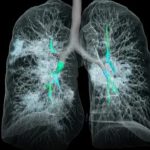

Las radiografías o Rayos X son una herramienta empleada en el campo de la Medicina para obtener imágenes del interior de los cuerpos al exponerlos a una fuente de radiación controlada.

A través de este método, se facilitan los diagnósticos médicos sin necesidad de cirugías exploratorias o invasivas.

Las imágenes de rayos X muestran el interior de su cuerpo en diferentes tonos de blanco y negro. Esto es debido a que diferentes tejidos absorben diferentes cantidades de radiación. El calcio en los huesos absorbe la mayoría de los rayos X, por lo que los huesos se ven blancos.